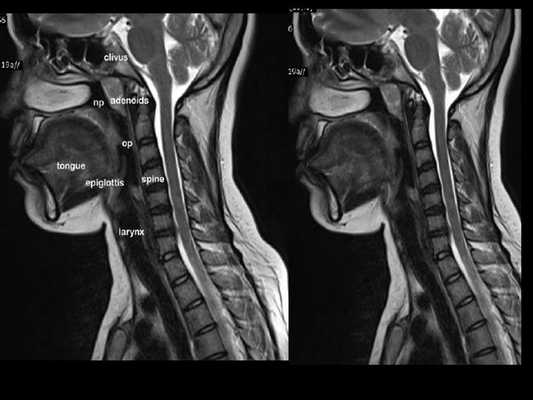

На фото МР-снимок органов лица, шеи и соответствующего отдела позвоночника

Патологии органов шеи могут проявляться незначительными симптомами или серьезно снижать качество жизни человека. Заболевания горла и гортани требуют точных методов диагностики, поскольку за периодической охриплостью голоса и другими признаками отклонений может стоять онкология. Чтобы получить достоверную информацию о происходящих в данной области процессах проводят магнитно-резонансную томографию. У пациента может возникнуть вопрос, что показывает МРТ горла и гортани. Метод отражает состояние мягких и костных тканей, нервной, сосудистой и лимфатической систем в шейном отделе позвоночника.

МР-томография - достоверный и безопасный способ диагностики заболеваний органов шеи и других областей. Пациент не подвергается лучевой нагрузке при исследовании. Магнитное поле приводит в возбуждение атомы водорода в тканях, датчики фиксируют измененный сигнал. Компьютер обрабатывает информацию и объединяет последовательные снимки в объемное изображение. Врач получает представление о том, как выглядят глотка, горло, гортань, трахея и шейный отдел позвоночника.